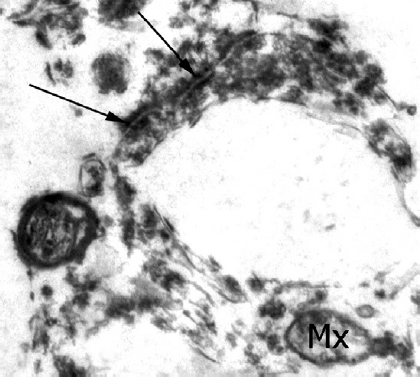

В связи с тем, что еще одним типичным признаком патологии альцгеймеровского типа является синаптическая дисфункция, нами были исследованы синапсы и установлено, что в изученном материале у всех умерших с БА практически всегда обнаруживались ультраструктурные изменения. В пресинаптической части синаптического аппарата митохондрии либо отсутствовали вовсе, либо их структура была нарушена; часто были разрушены митохондриальные матрикс и кристы, при этом сами митохондрии становились почти прозрачными (рис. 4). Обнаруживались различные изменения синаптических везикул: с одной стороны, они были слипшимися, с другой — разрушенными и нередко располагались на расстоянии от синаптической щели. Непосредственно зона синаптического контакта характеризовалась повышенной плотностью, особенно в постсинаптической части, при этом терминали, прилежавшие к этой зоне контакта, нередко были прозрачными. Кроме того, в некоторых синаптических терминалях наблюдались картины грубогранулярного распада всего синаптического комплекса, т. е. синаптических везикул, митохондрий и собственно синаптической щели [2].

Рис. 4. Многополюсный синапс при деменции альцгеймеровского типа. Мх — митохондрия, стрелки — зоны синаптических контактов. Ув. ×25 000

Fig. 4. Multipolar synapse in dementia of the Alzheimer’s type. Mx —mitochondrion, arrows — synaptic contact zones. Magn. ×25,000